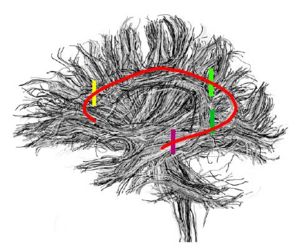

Arcuate Fasciculus

These labelmaps ('caseD00XXX-FS-arcuate-final.nhdr') were created using automatic gray matter parcellation in Freesurfer and coregistered in Slicer to corresponding DTI dataset. The labelmaps were dilated in Slicer to increase coverage of gray matter.

Figure 12. Gray matter ROI's for Arcuate Fasciculus tractography

Figure 13. Gray matter ROIs (right side) in 3D

The color coding of the resulting ROIs is as follows:

ROI 1: Superior Temporal Gyrus - Left(5) - Right(6)

ROI 2:Inferior Frontal Gyrus- Left(13) - Right (14)